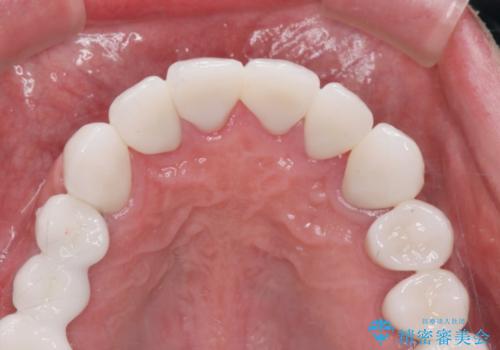

セラミッククラウンを除去し仮歯を装着し、歯周外科手術を行い歯ぐきの状態を改善したのち、適合の良いセラミッククラウンを再作製をする治療計画としました。

- 90.2万円(ジルコニアクラウン×6・仮歯×6 ・歯周外科手術)費用は治療当時の料金となります

見た目の良いクラウンが装着されていても、歯ぐきの状態が悪ければ違和感や歯ぐきの腫れ、臭いの元となっていることが多く見られます。